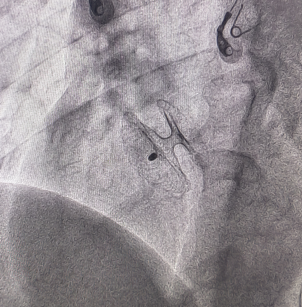

Case 4

卵圆孔隧道长12mm,裂隙直径3.2mm。房间隔探及左向右约4mm的分流束。应用D-shufo 3036-6 PFO封堵器成功封堵。